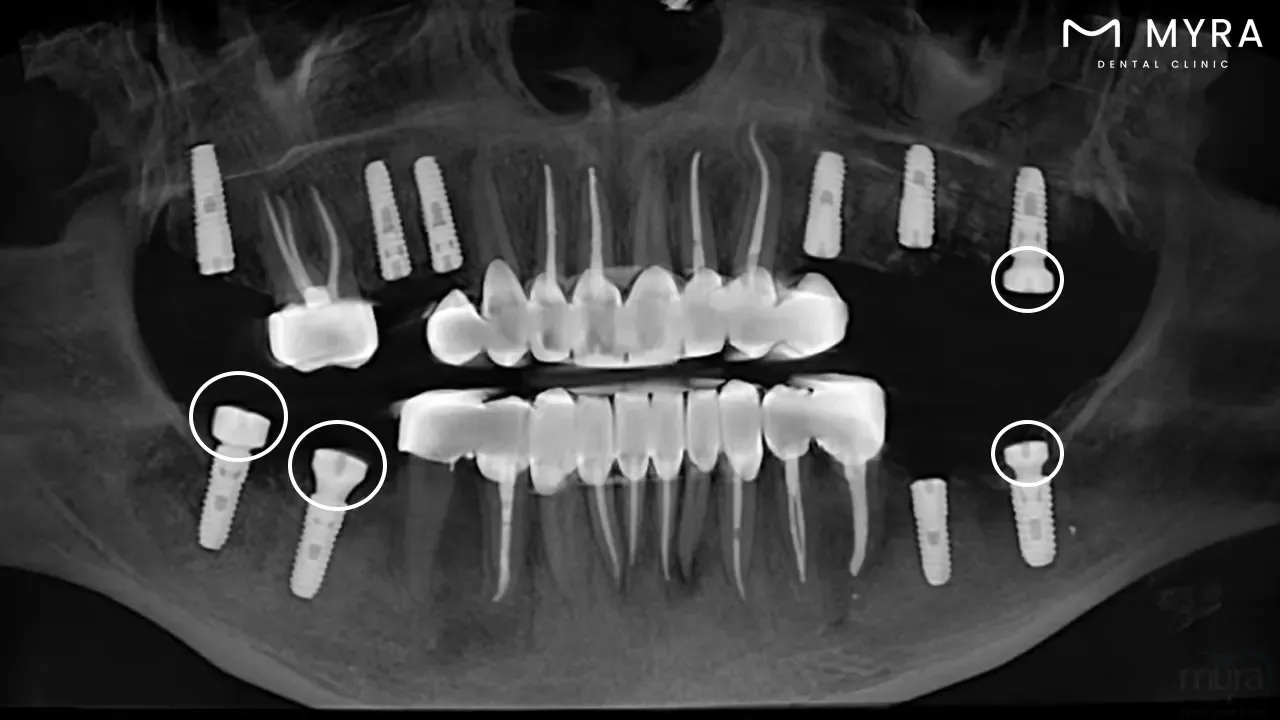

A dental implant healing cap, referred to as an abutment, is a small device affixed to a prosthesis through surgery. The dental implant healing cap safeguards the implant by serving as a protective cover while the surrounding gum tissue heals and bonds to it.

A healing cap is referred to as a gingival former or abutment. A small piece is used to place dental implants that form the gum line, keep plaque away, and allow the tissue to heal the implant. It is placed on top of the prostheses when a dental implant is surgically placed into the jawbone. Others ask, “What is a healing cap on a dental implant?” It serves as a protective cover while the surrounding gum tissue heals and bonds to the implant. The healing cap for implant is designed to maintain the shape and contour of the gum tissue during the healing process, which takes several weeks to several months. It is taken out and replaced with a new dental crown or bridge after healing. An essential component of the intricate implant process is correctly integrating the implant with the surrounding bone and gum tissue.